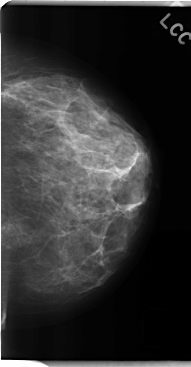

C_0194_1.LEFT_CC

LEFT_CC LINES 4768 PIXELS_PER_LINE 2472 BITS_PER_PIXEL 12 RESOLUTION 50 NON_OVERLAY